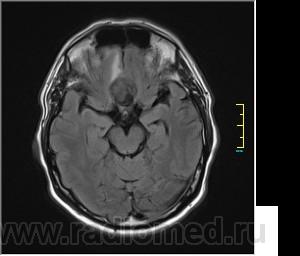

Пациентка направлена на исследование с диагнозом "Гипертонический криз", энцефалопатия неуточненная.

Ax T2 Flair:

частично функционирующая аневризма

Иначе говоря, аневризма с хронической геморрагией, т.к. мы видим фракции крови различного возраста.

По-моему, аневризма с пристеночными тромбами.

Постепенное пристеночное образование тромбов приводит к появлению типичного для аневризмы феномена -слоистости МР сигнала в полости аневризмы. Данная картина демонстрирует слоистый характер тромботических масс в полости аневризмы .Функционрирующая часть имеет низкий сигнал во всех режимах сканирования. Дополнительно-перифокальный отек.

А может более корректно интерпретировать как частично тромбированная аневризма... Уж коь речь идет о фракциях, ну то есть о тромбе по сути.... Ну и плюс перфокальный отек головного мозга (вероятнее цитотоксический+вазогенный).